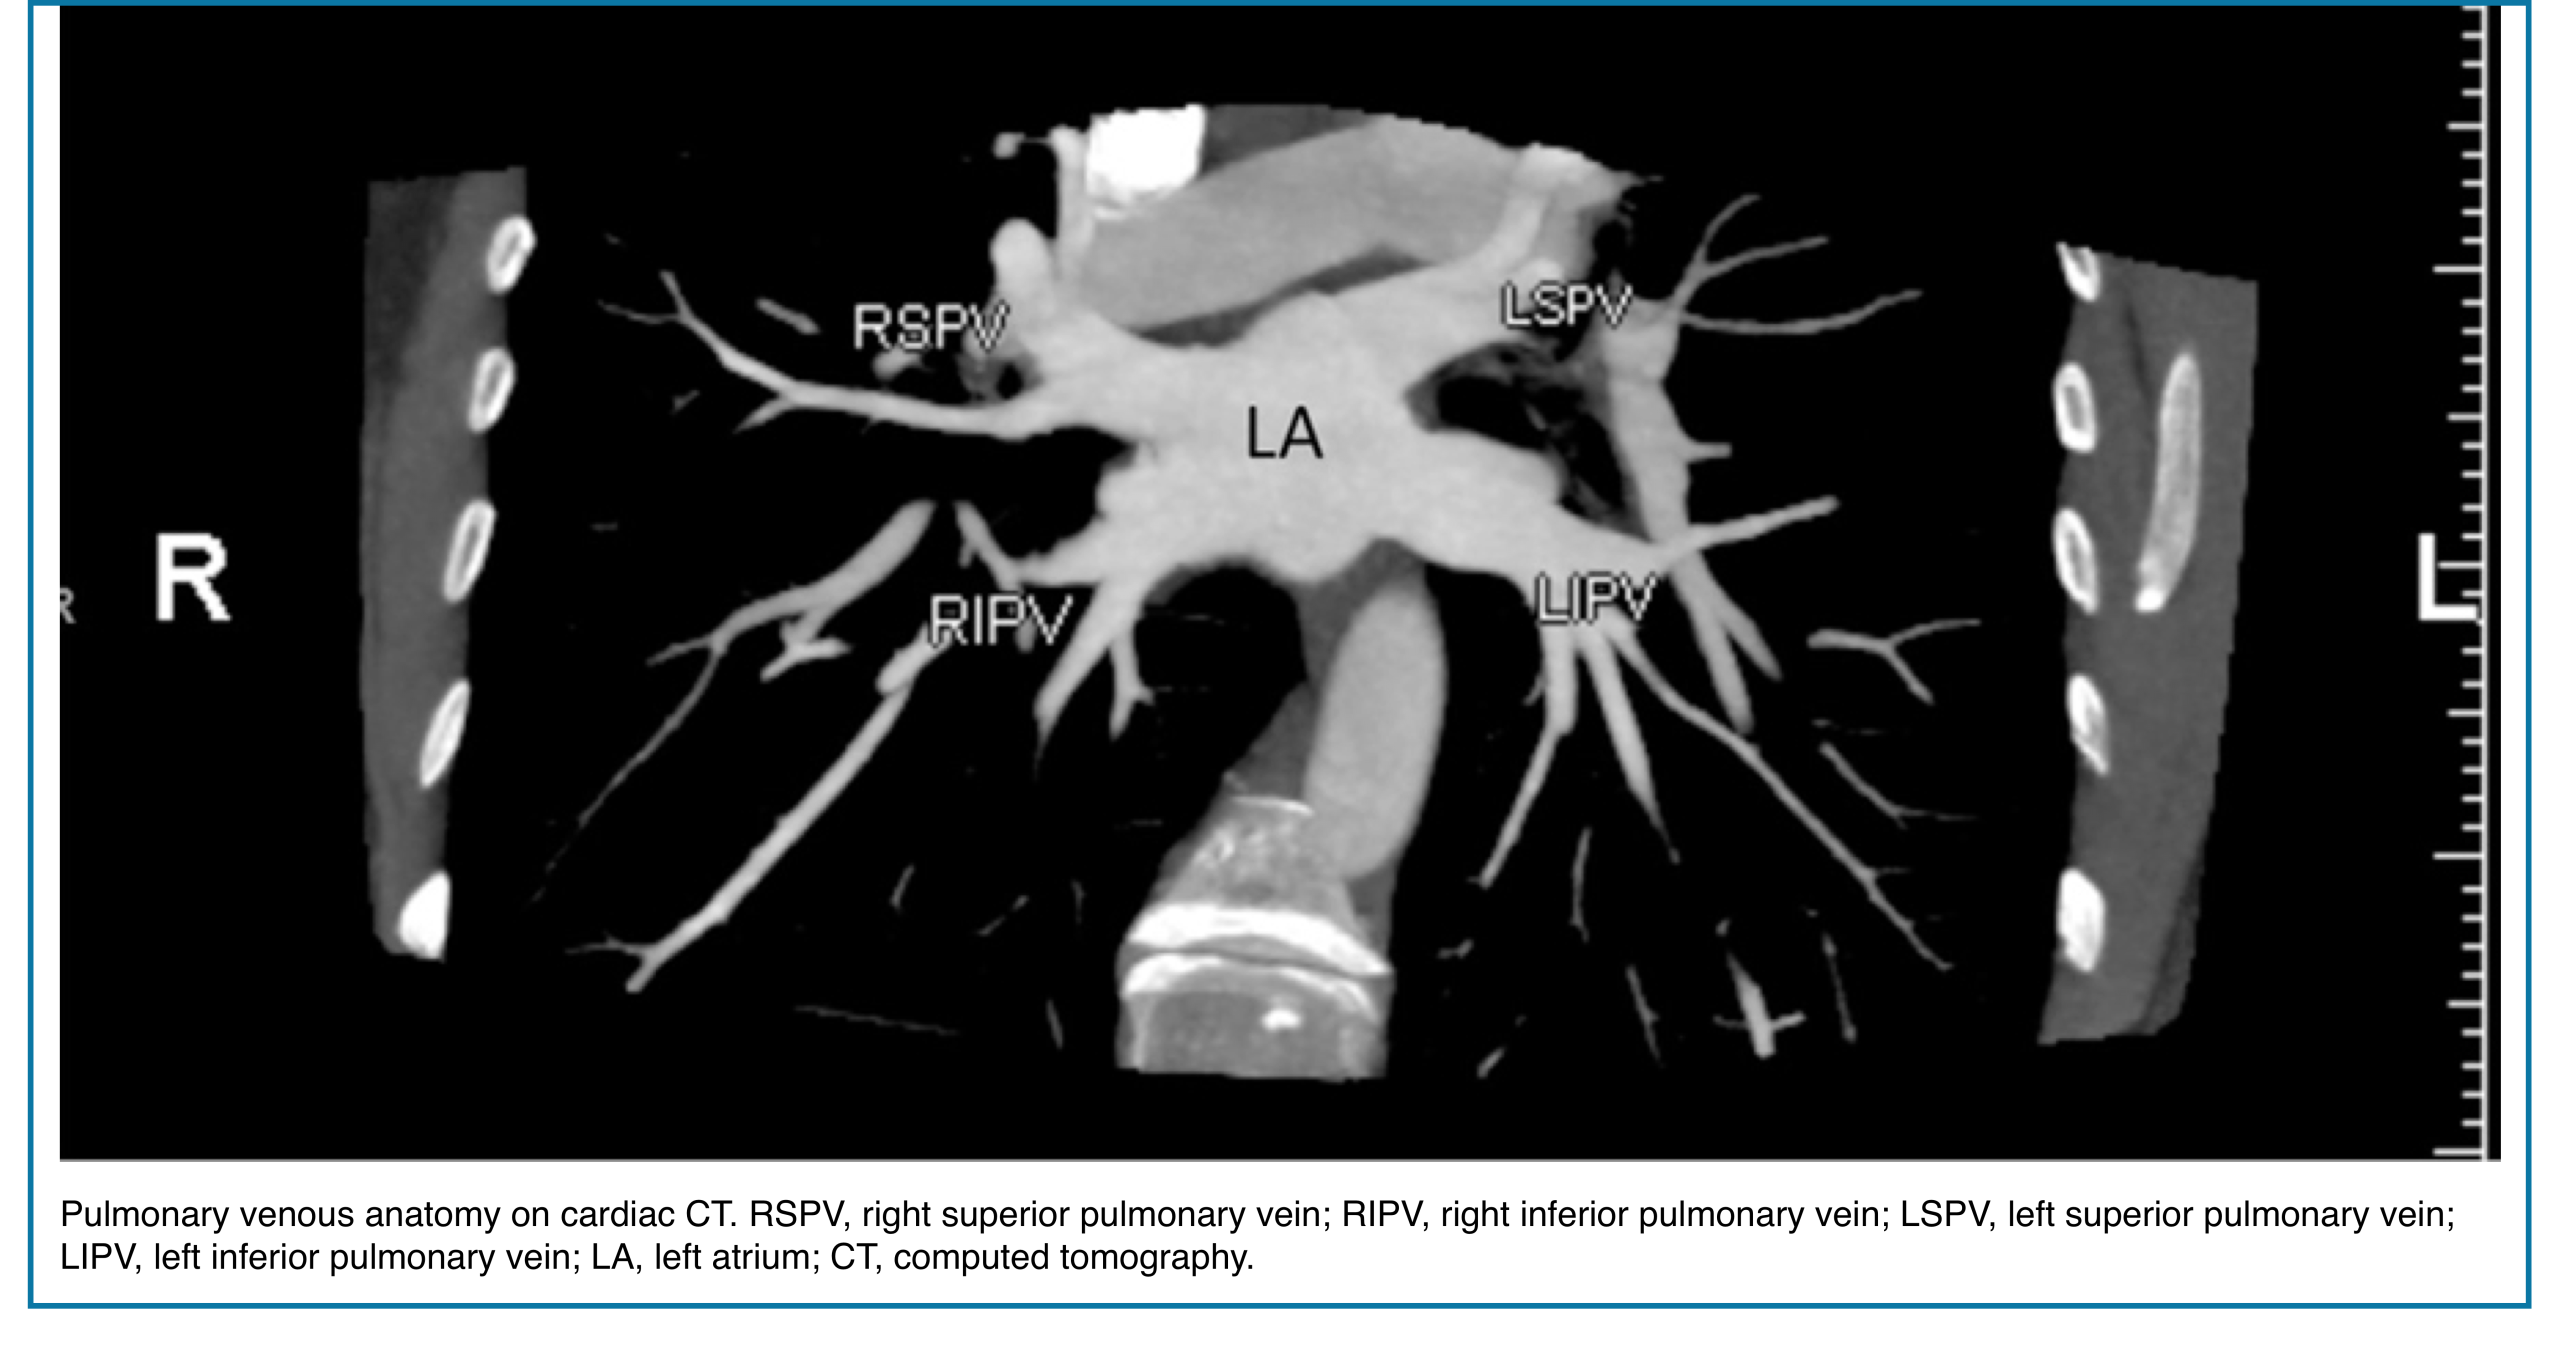

◾️Pulmonary vein anatomy:

- Typically, there are four pulmonary veins with superior and inferior pulmonary veins on either side, draining into the left atrium (Right figure below).

- In both hilae, the superior pulmonary vein is the most anterior structure and the inferior pulmonary vein is the most inferior structure.

- The parenchymal pulmonary vein branches run within interlobular septa and do not parallel the segmental or sub-segmental pulmonary artery branches and bronchi.

💡 Pulmonary Artery Course: Quick Pearl

- Upper lobe arteries run central to their bronchi.

- Middle lobe, lingular, and lower lobe arteries run peripherally to their bronchi.

- Pulmonary veins usually lie anterior to the arteries, except in the right upper lobe, where venous position is more variable.